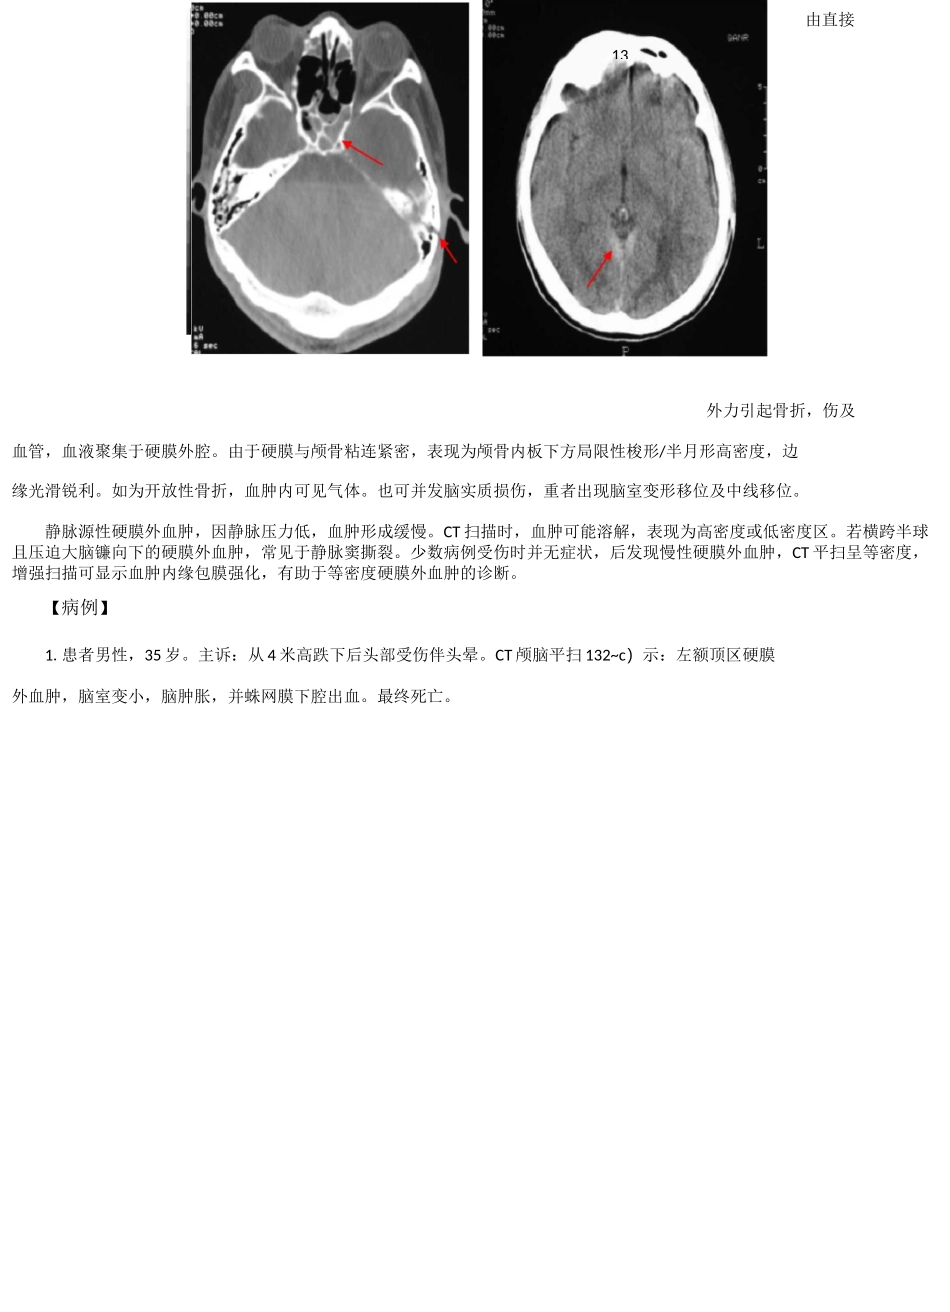

2.患者男性,33 岁。主诉:头部外伤半小时,昏迷。查体:左外耳道及右鼻腔鲜血。CT 颅脑平扫 1-3-1~d)示:左眼眶骨折,硬膜外少量积气,双筛窦及蝶窦内积血。左乳突部骨折及蛛网膜下腔出血。由直接一、颅骨损伤第三节颅脑损伤CT 对颅骨骨折可见到骨碎片及凹陷骨折的深度,同时窦、筛窦等诸窦腔的积血。对开放性骨折可见血肿内、脑胀及血肿也易显示。【病例】膜下腔积气上颌窦、蝶筋膜下的肿1.患者男性,69 岁。主诉:头、胸部外伤 12 天,一过性意识丧失。CT 颅脑平扫 1-3-1~b)示:右额叶皮质少量出血,额骨及左枕骨线性骨折,左枕帽状筋膜下水肿。外力引起骨折,伤及血管,血液聚集于硬膜外腔。由于硬膜与颅骨粘连紧密,表现为颅骨内板下方局限性梭形/半月形高密度,边缘光滑锐利。如为开放性骨折,血肿内可见气体。也可并发脑实质损伤,重者出现脑室变形移位及中线移位。静脉源性硬膜外血肿,因静脉压力低,血肿形成缓慢。CT 扫描时,血肿可能溶解,表现为高密度或低密度区。若横跨半球且压迫大脑镰向下的硬膜外血肿,常见于静脉窦撕裂。少数病例受伤时并无症状,后发现慢性硬膜外血肿,CT 平扫呈等密度,增强扫描可显示血肿内缘包膜强化,有助于等密度硬膜外血肿的诊断。【病例】1.患者男性,35 岁。主诉:从 4 米高跌下后头部受伤伴头晕。CT 颅脑平扫 132~c)示:左额顶区硬膜外血肿,脑室变小,脑肿胀,并蛛网膜下腔出血。最终死亡。由直接132.患者男性,69 岁。主诉:右下肢活动不利伴头晕 5 日。既往脑血栓病史 9 年。CT 颅脑平扫 1-3-2~b)示:左额部硬膜外亚急性血肿,左额叶轻度受压。3.患者女性,87 岁。主诉:右侧肢体活动不利 4 天。CT 颅脑平扫 1-3-2~c)示:左侧硬膜外复合型血肿,血肿呈混杂密度,左侧脑室受压变形,中线移位。1.患者男性,74 岁。主诉:脑外伤后 1 天,昏迷。CT 颅脑平扫 1-3-3~c)示:右额叶局限性血肿,左顶三、硬膜下血肿发生在硬脑膜与蛛网膜之间的血肿。由于蛛网膜无张力,与硬脑膜连接很薄弱,故血肿范围较广。形状大多呈新月状,可超过颅缝,甚至可占据整个大脑半球的硬脑膜下腔。可分急性、亚急性、慢性,以亚急性多见。急性时间在 3 天以内。CT 表现为高密度,个别也可为混杂密度、等密度甚至低密度(系蛛网膜破裂,脑脊液进入血肿所致,或患者严重贫血)。亚急性时间为 4 天至 3 周,系急性向慢性发展的过渡阶段。CT 表现的形态及密度均多样化。形态可有新月形...